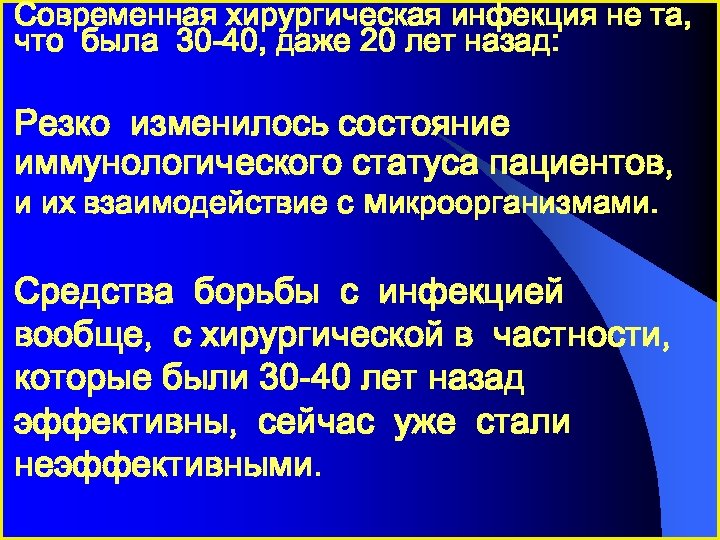

Современная хирургическая инфекция не та, что была 30 -40, даже 20 лет назад: Резко изменилось состояние иммунологического статуса пациентов, и их взаимодействие с микроорганизмами. Средства борьбы с инфекцией вообще, с хирургической в частности, которые были 30 -40 лет назад эффективны, сейчас уже стали неэффективными.

Современная хирургическая инфекция не та, что была 30 -40, даже 20 лет назад: Резко изменилось состояние иммунологического статуса пациентов, и их взаимодействие с микроорганизмами. Средства борьбы с инфекцией вообще, с хирургической в частности, которые были 30 -40 лет назад эффективны, сейчас уже стали неэффективными.